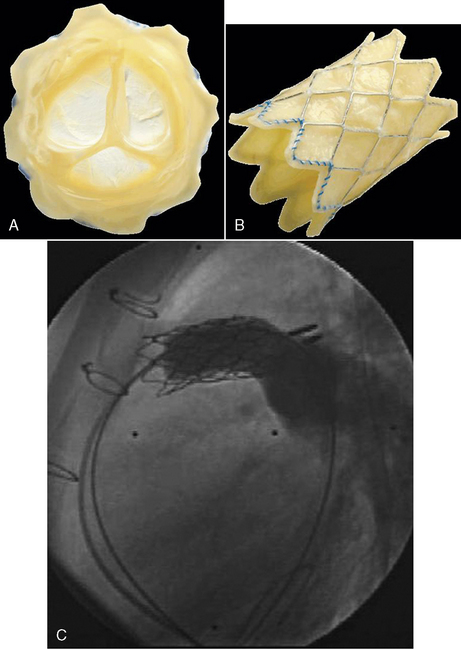

Coronary Artery Fistulas

In rare cases, spontaneous closure of a fistula has been reported. Intervention is recommended only if symptoms are present. In some cases coil occlusion of the fistula is possible during cardiac catheterization. Otherwise, surgery is performed through a median sternotomy incision and usually requires cardiopulmonary bypass. The fistula is identified, approached through the vessel or chamber, and sutures are used to close the connection. Without treatment the natural history of these defects has not been clearly determined, but surgical and hospital mortality, rate of complications, and late mortality are all very low.497